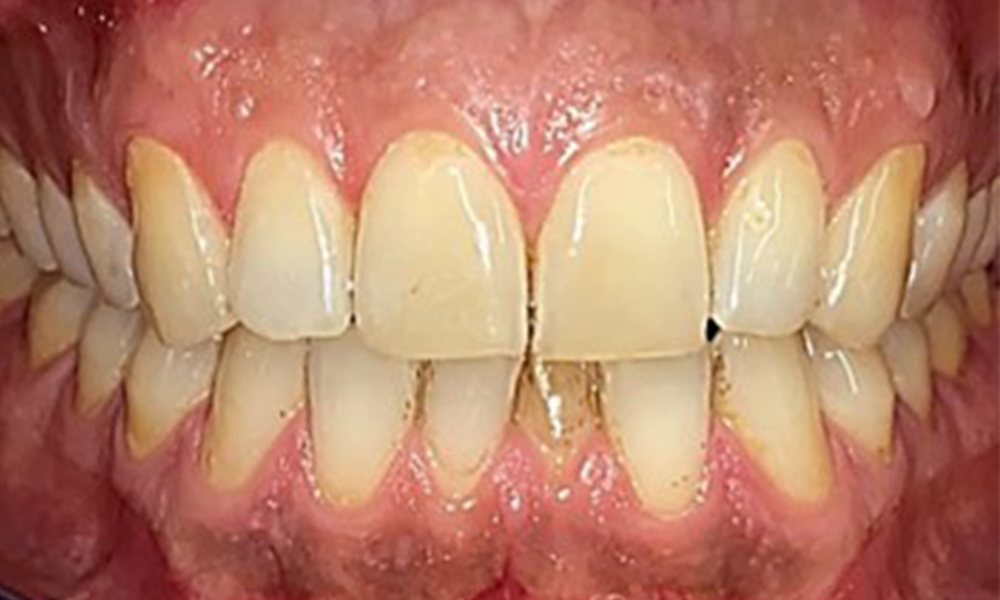

Vue de face

Fig. 2 Vue de face, © Dr R. Krapf

Il n'y a pas eu de résultats pathologiques extra-oraux. Lors de l'examen intrabuccal, l'inspection de la vue frontale a révélé une décoloration brunâtre près de la gencive kératinisée et à la transition vers la muqueuse mobile (Fig. 2), qui pourrait être attribuée à la consommation de nicotine. Des lésions blanchâtres de la muqueuse ont été observées sur le palais, en particulier près des surfaces palatines des molaires maxillaires, ce qui indique une kératinisation accrue et peut également être attribué à la consommation de nicotine. La langue était recouverte d'un enduit amovible blanc et brunâtre.